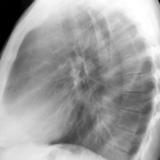

RLL Collapse 3 PA only

Date: 02/28/2004

Views: 3116